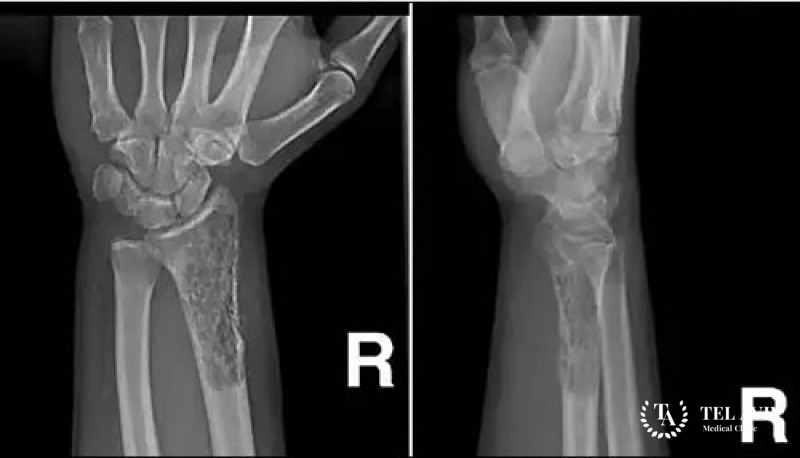

Для диагностирования заболевания необходимо провести подробное гистологическое исследование опухоли. Лейомиосаркома обладает характерными признаками. Если клиническая картина не прояснилась после гистологии, проводят иммуногистохимические обследования. При наличии подозрений на гематогенное метастазирование необходима рентгенография грудины, сцинтиграфия костных, скелетных тканей.